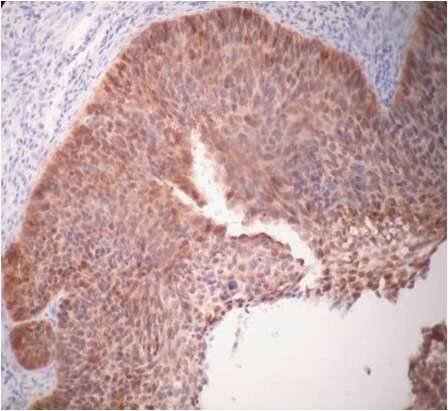

LCIS, proliferace uniformních okrouhlých buněk se sníženou soudržností

Lobulární karcinom in situ (LCIS)